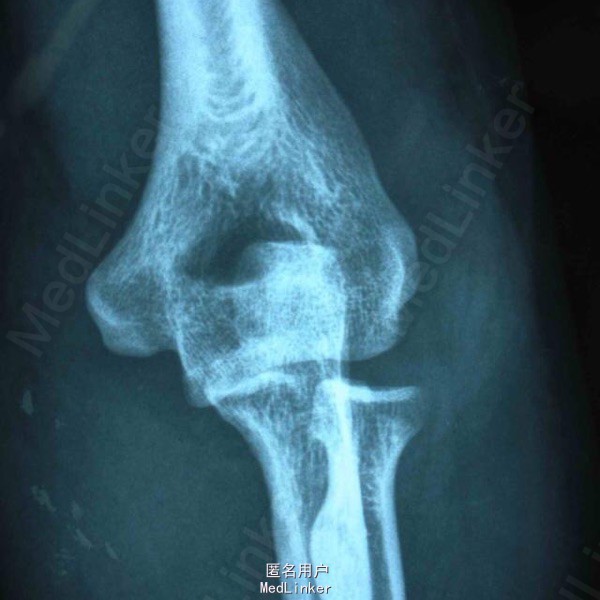

手法复位后X片及术后正侧位 初步诊断:左肘关节损伤三联征。治疗过程:尺骨冠状突骨折块复位固定、桡骨小头骨折块复位固定、内外侧副韧带修复、可活动式外固定支架固定。

对于术后选择石膏固定还是铰链式外固定支架固定,主要考虑哪种外固定有利于术后功能恢复。肘关节损伤三联征主要的并发症:僵硬,复发性不稳定,异位骨化。避免僵硬发生的有效手段就是术后即可以活动(主动或被动)肘关节,石膏固定显然不能达到术后即开始活动肘关节,如果用石膏固定最短需要 2 周(有人建议 7~10 天),如果骨折固定较稳定,没有再移位或复发脱位的倾向,2 周时间是可以的,如果有骨折再移位或复发脱位的倾向,2 周时间可能不够,需延长至 4 周或 6 周。 此时肘关节才能开始活动,僵硬的机会已很大。铰链式外固定支架固定后,患者术后次日即可以主动活动肘关节,也可被动活动,同时外固定支架可施加牵引力有效保护冠状突及桡骨头骨折不再移位,保护修复后的内外侧副韧带复合体不被牵拉撕裂,关节复发脱位不再出现。 去掉外固定架的时间取决于肘关节的稳定性、骨折愈合情况、关节活动度增加和针道状况等。外固定架固定肱尺关节 3~6 周,有人建议外固定架平均使用时间为 8 周 (6—10 周)。术后 8 周后允许非限制性的关节活动锻炼。